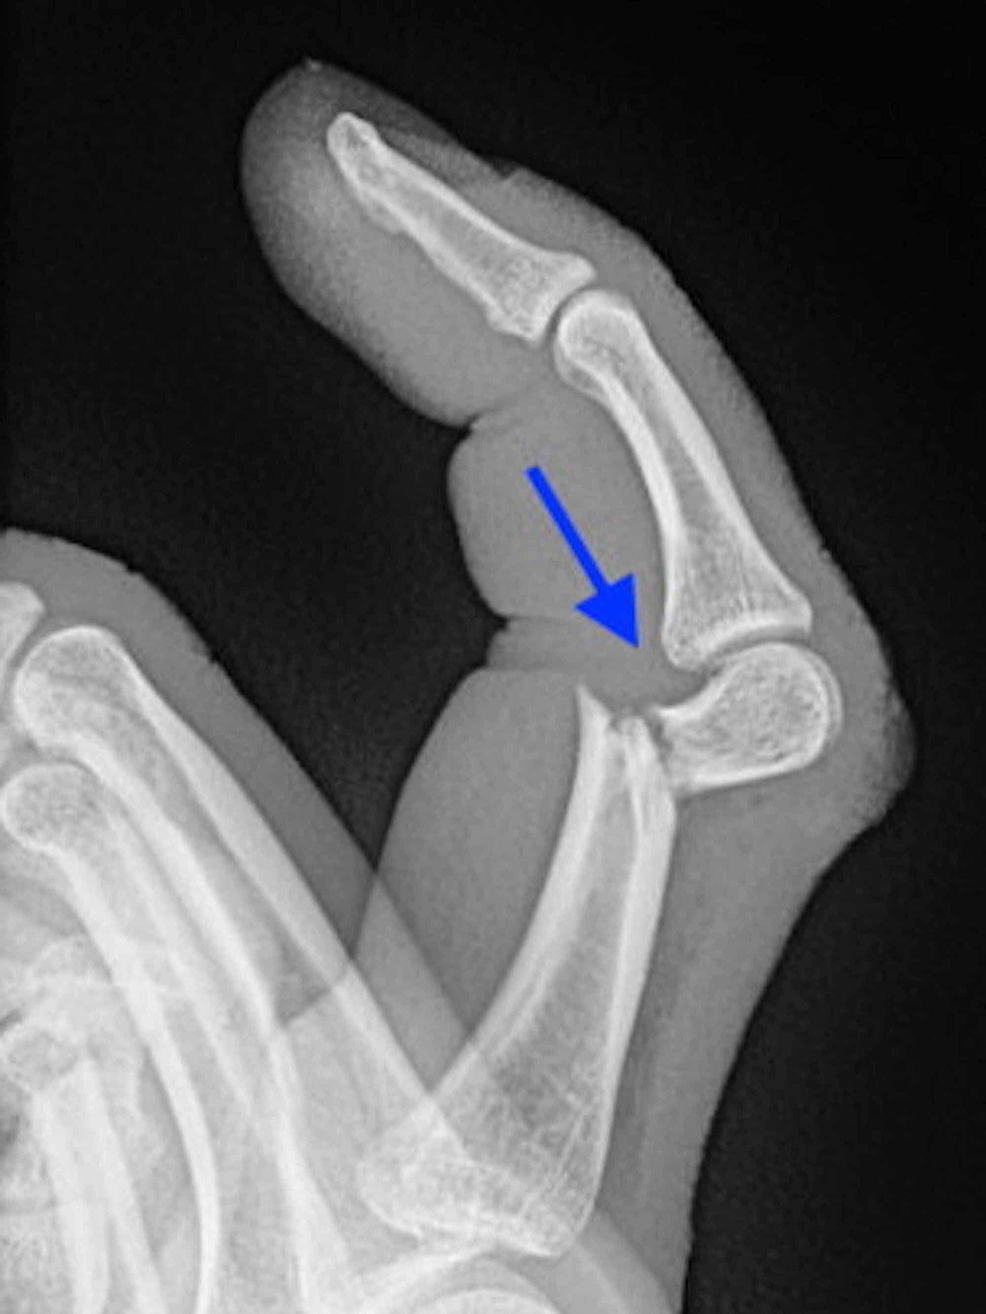

손가락 골절은 기저부(base) 골절, 중간부(shaft) 골절, 관절면(intra-articular) 골절 등으로 나뉘며, 특히 관절면을 침범한 골절은 기능적 후유증이 남을 위험이 높습니다. 따라서 엑스레이 검사로 정확한 위치와 손상 정도를 파악하고, 필요 시 CT나 초음파로 인대 손상 여부를 함께 확인해야 합니다.

손가락에 금이 갔을 때 무조건 깁스를 해야 하는 것은 아닙니다. 뼈가 어긋나지 않은 단순 골절이라면 스플린트나 버디 테이핑만으로도 충분히 치료가 가능합니다. 깁스는 뼈가 크게 전위되었거나, 여러 조각으로 부서졌을 때, 혹은 골절선이 관절면을 침범해 안정적인 고정이 필요한 경우에만 시행합니다.

손가락에 금이 갔을 때 중요한 것은 정확한 진단입니다. 단순히 통증이 있다고 해서 자가진단으로 테이핑만 하는 것은 위험하며, 반드시 엑스레이 검사를 통해 뼈의 정렬 상태와 골절선을 확인해야 합니다.